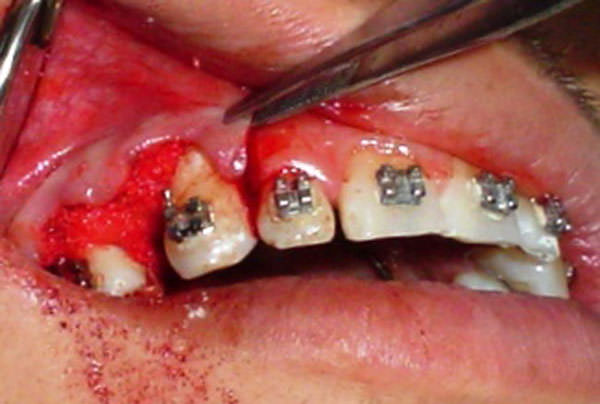

Una vez tomada la radiografía una semana antes de la cirugía, se realizó una incisión crestal y la eliminación del periostio con elevación del colgajo hasta tener la cresta ósea al descubierto (fig.3). Luego se realizó una fractura controlada con una expansión debido a la elasticidad de la cortical con martillo y cincel (fig.4) hasta obtener un surco de 0.3mm de anchura y 5mm de diámetro de profundidad permitiendo la separación de ambas tablas sin rotura.

Figura 3

Eliminación del periostio con elevación del colgajo para obtener la cresta ósea al descubierto.